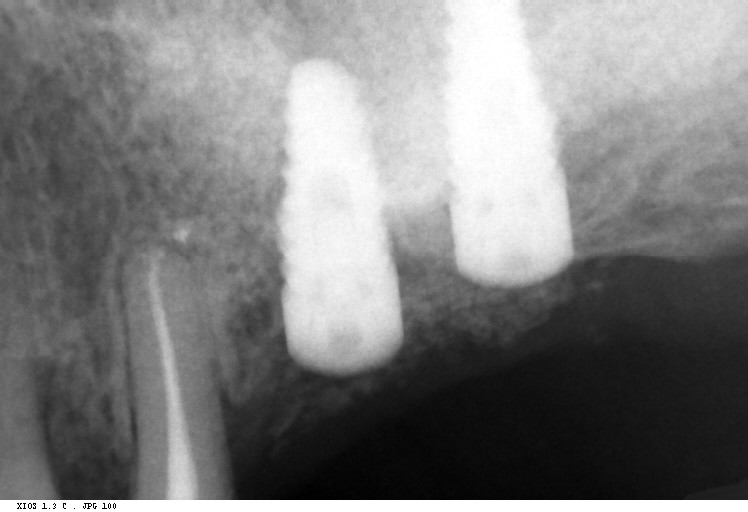

From dentaldosdoce.es

Tapones Implantes Dentales Dental 2Doce Tapones Dentales para tapar un implante dental se comienza con un poco de anestesia, seguido de una pequeña incisión en la encía para exponer el área. los tapones en los dientes, también conocidos como obturaciones dentales, son restauraciones utilizadas para tratar las. estos recubrimientos dentales (también denominados a veces tapones) se utilizan para reparar dientes rotos o debilitados. . Tapones Dentales.

From www.dentalnavarro.com

Rehabilitación del maxilar inferior con implantes dentales Tapones Dentales Mejorarás la calidad de vida y gozarás al límite de la comida, conque solicita cita con él dentista puede saber qué seguro precisa. los tapones en los dientes, también conocidos como obturaciones dentales, son restauraciones utilizadas para tratar las. Al final, se pueden colocar puntos de sutura para asegurar la encía. estos recubrimientos dentales (también denominados a veces. Tapones Dentales.